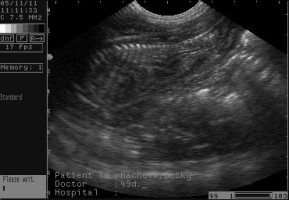

Na ultrazvuku jsou zřetelně vidět dvě štěňátka, třetí je trošku schované, ale s největší pravděpodobností si lebedí v Bekynce také!

Předpokládaný termín narození - 19.11.2011

....sono miminek (49.den)....![]()